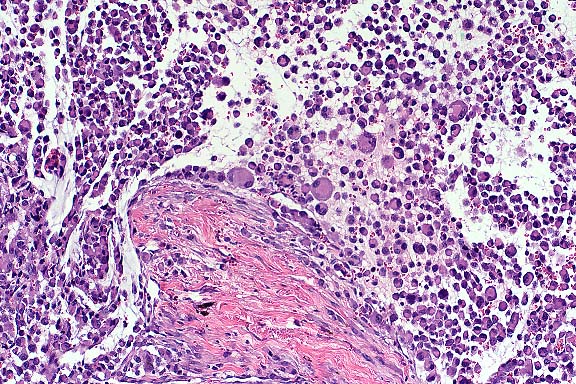

Case 1: Liver. Note focus of coagulative necrosis, mild infiltration of lymphocytes and plasma cells, and scattered hepatocytes containing eosinophilic intranuclear inclusions.(40x obj)

1. Liver: Hepatitis and cholangitis, necrotizing, multifocal, random, acute, mild, with eosinophilic intranuclear inclusion bodies, Muscovy duck, avian, etiology consistent with duck herpesvirus 1.

Conference Note: Duck virus enteritis (DVE) is a highly contagious and often fatal alpha-herpesviral infection of ducks, geese, and swans. This disease is enzootic in North America and has been reported in Europe, Asia, and India. DVE can be transmitted by direct contact, or indirectly by contact with a contaminated environment. Experimentally, it can be transmitted via oral, intranasal, intravenous, intraperitoneal, intramuscular, and cloacal routes. Potential transmission by bloodsucking arthropods may be possible during viremia. A carrier state has been suspected in wild ducks.

Histologic lesions include gastrointestinal necrosis, hepatocellular necrosis, necrosis and loss of lymphoid tissue, and necrotizing vasculitis. As in this case, eosinophilic intranuclear viral inclusion bodies are present in hepatocytes, biliary epithelium, gastrointestinal epithelium, and lymphoreticular cells associated with these necrotizing lesions. Intranuclear inclusions have also been reported in vascular endothelium. As the contributor observed, some of the esophageal epithelial cells contain eosinophilic intracytoplasmic inclusion bodies. While these inclusions may be poxviral inclusions, conference participants noted that intracytoplasmic herpesviral inclusions have been reported in a natural outbreak of DVE in muscovy ducks.2